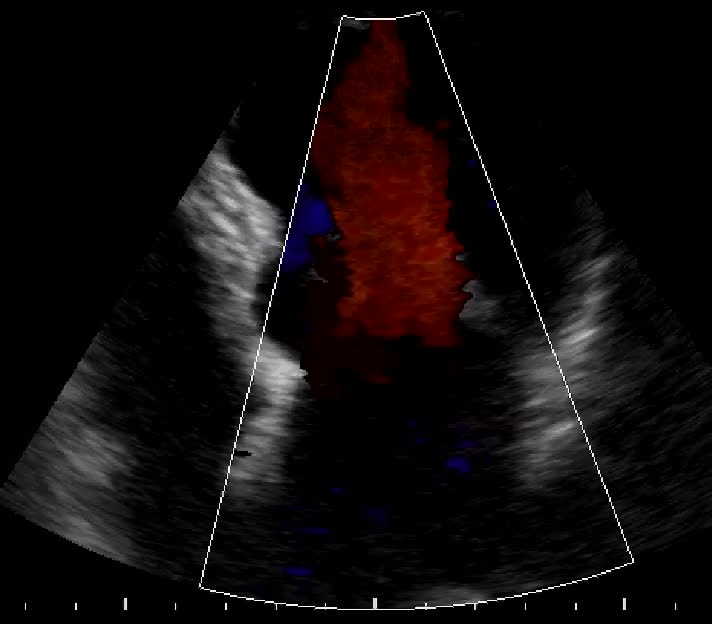

Insufficienza tricuspidale severa

Daniela Torta

Antonio Mantero